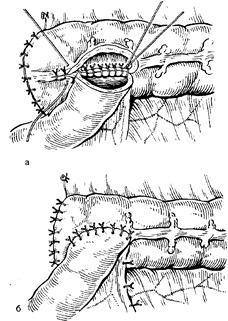

Ábra. 12. Jobb oldali hemicolectomy. Műveleti lépésekben.

és - vágás a hátsó parietális hashártya a vakbél jobbra az első kanyarban;

b - Tanszék vak colon ascendens az ő média-line (alján a seb látható húgyúti Točník); in - a kereszteződés hepatocelluláris ínszalag; g - a kereszteződés gasztrointesztinális ínszalag; d - vágás a belső réteg Bry-zheyki vastagbél (NE-kereszteződés helyeken csípőbélben és keresztirányú vastagbél-set mondta példány: 1 - A jobb oldali ág közepén kólika artéria; 2 - Jobb kólika artéria; 3 - vastagbél csípőartériába.

Kérelemre ileotransverzoanastomoza oldalán-oldalra anasztomózisok csípőbél hurkot keresztirányú-sósav vastagbél isoperistaltic, t. E. Végeiket két oldalán helyezkednek el (vége a vékonybélben mentén fekszik a vastagbél) (13.).

Ábra. 13. előírása csípőbél-transverzoanastomoza oldalról a másikra.

és - alakítás a hátsó fal-ki; b - alakítás elülső falának az anasztomózis.